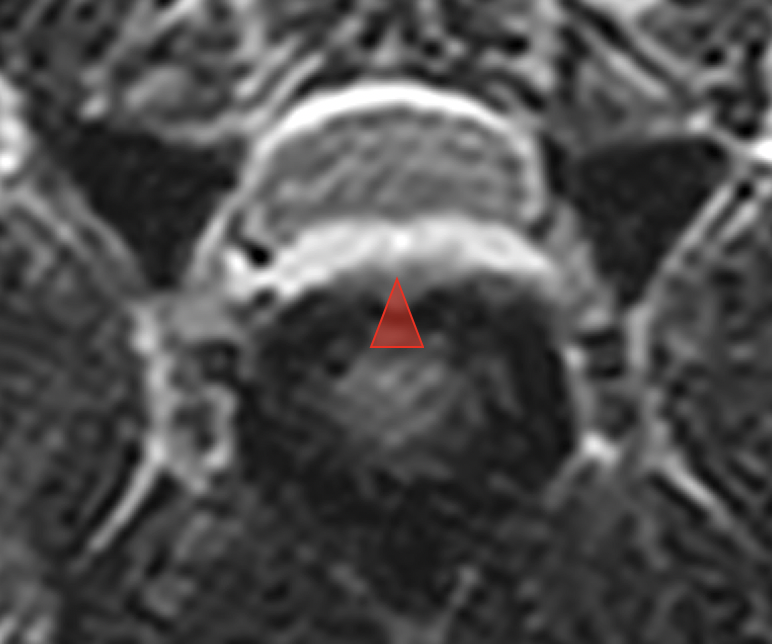

病変部位のMRI(T2WI横断):逸脱した水和髄核は白くカモメのような特徴的な形態を示す